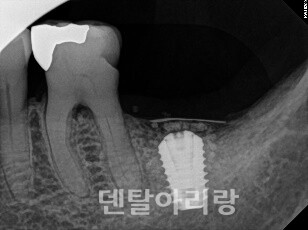

△그림 13. 치조정 접근법에 의한 임플란트 식립 후, 상악동내 출혈

이런 경우, 구강 내로는 출혈이 없이 상악동과 상악동을 통해 비강으로 연결되는 매우 심각한 비출혈이 일어나며, 지혈이 어렵기 때문에 대부분 응급 상황으로 이어지게 된다. 따라서, 치조정 접근법을 통해 임플란트 식립 후, 구강내 출혈이 없더라도 환자가 수술 직후, 또는 귀가 후에 다량의 비출혈 증상을 호소하면 응급실을 통한 구강악안면외과 전문의에게 즉시 의뢰하여야 한다.